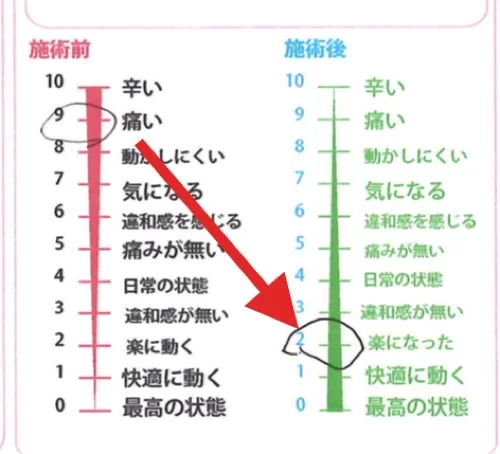

施術前 9 :痛い → 施術後 2 :楽になった